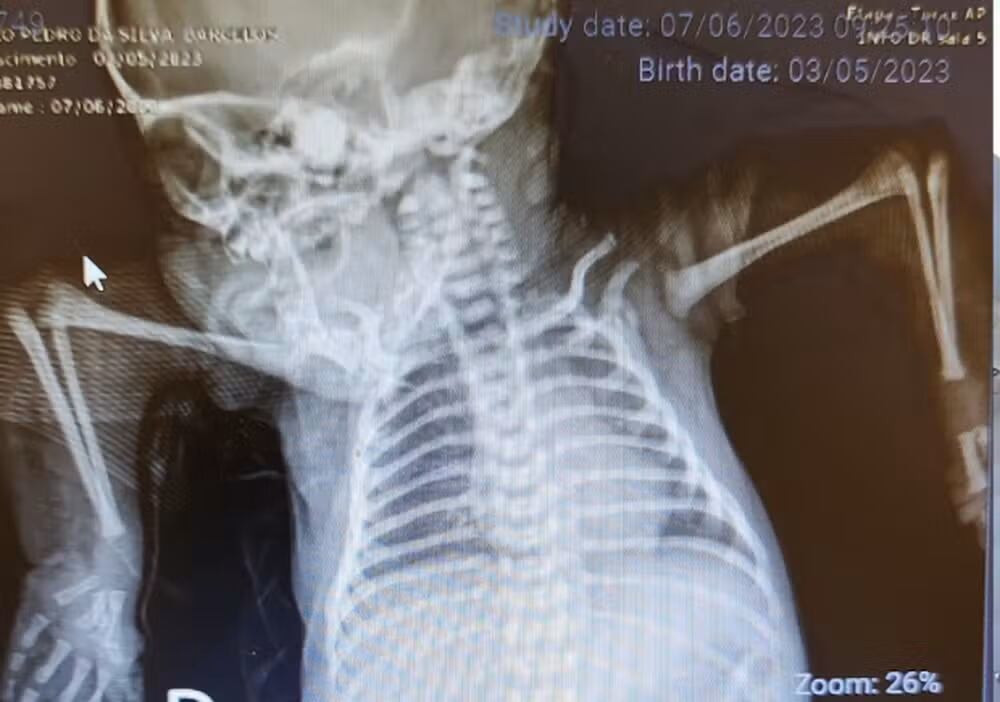

João Pedro nació con los hombros posicionados hacia abajo y los codos orientados hacia arriba. Además, sus articulaciones estaban rígidas y acortadas, lo que le impedía mover los brazos o los dedos.

El bebé fue trasladado al Instituto Nacional de Traumatología y Ortopedia de Brasil, donde inició tratamiento.

A los seis días de nacido, João Pedro utilizó una tala improvisada hecha con ataduras y esparadrapo, pero sufrió una reacción alérgica. La terapeuta diseñó entonces una órtesis especial, hecha con material suave, que se colocaba sobre la ropa para evitar lesiones.

Con el tiempo, se elaboraron múltiples órtesis que se ajustaban al crecimiento y los cambios en la posición de sus brazos.